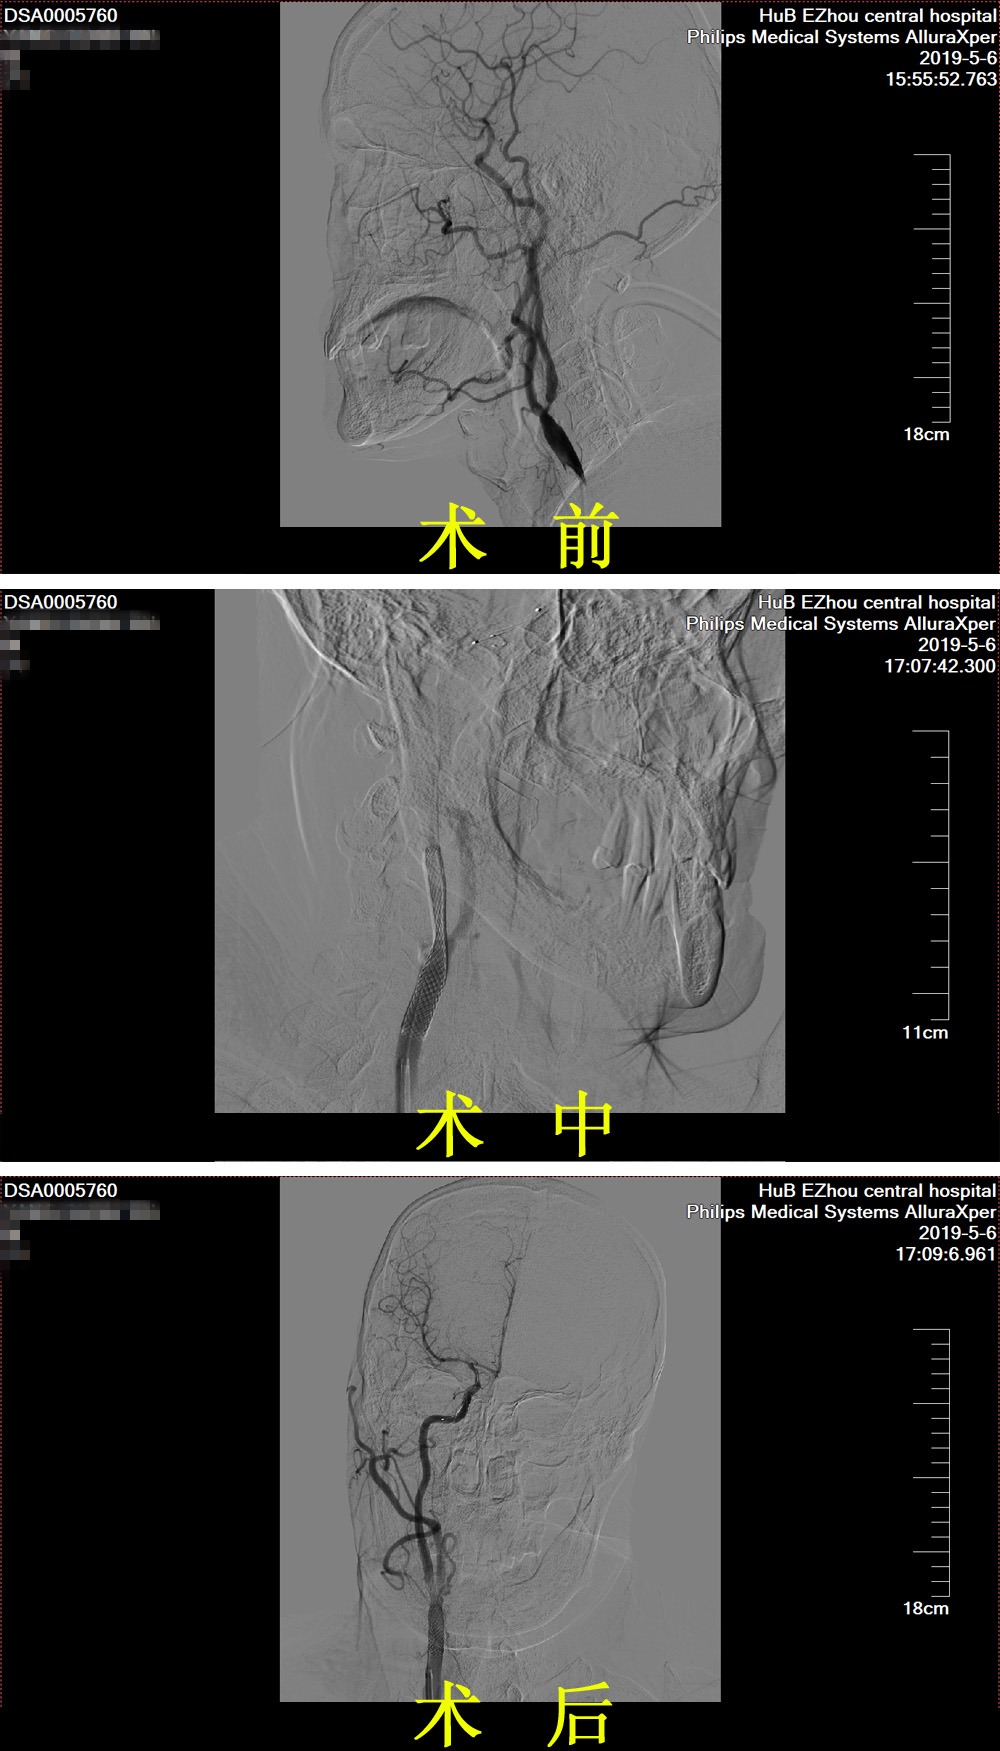

5月7日,经患者及家属签字同意后,鄂州市中心医院卒中中心团队给杨爹爹在介入室局麻下行经皮股动脉穿刺术+右颈内动脉球囊扩张+右颈内动脉支架植入术。经过术前各项准备后,在手术团队的精诚协作下,医生先在患者右侧颈内动脉远端颈颅交界处置入保护伞装置并释放,再于狭窄处用球囊预扩张,复查造影显示扩张满意后,最后再将支架成功置入狭窄处。术后,经多角度造影提示,患者右侧颈内动脉狭窄改善满意,手术顺利完成。目前患者恢复良好,已经能自行下床行走,日常生活尚能自理。